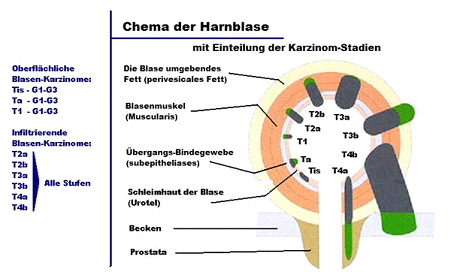

Определение стадии рака мочевого пузыря не менее важно для правильного лечения, чем своевременное диагностирование. Стадия определяется по размеру опухоли, степени ее прорастания в оболочки мочевого пузыря, поражению внутренних органов и лимфатической системы. Однако опухоль мочевого пузыря имеет свои особенности. На первых трех стадиях учитывается исключительно степень прорастания опухоли в оболочки пузыря: подслизистую, слизистую, серозную и подмышечную. Еще один способ определить стадию заболевания — оценить наличие и количество метастазов.

Стадия I |

T1 |

N0 |

M0 |

Стадия II |

T2a-b |

N0 |

M0 |

Стадия III |

T3a-T4a |

N0 |

M0 |

Стадия IV |

T4b |

N0 |

M0 |

Любая T |

N1 - 3 |

M0 |

Любая T |

Любая N |

M1 |